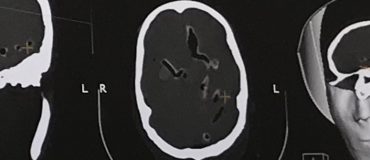

Des chercheurs sont parvenus à focaliser des ondes ultrasonores à travers le crâne grâce à des modèles de calcul...